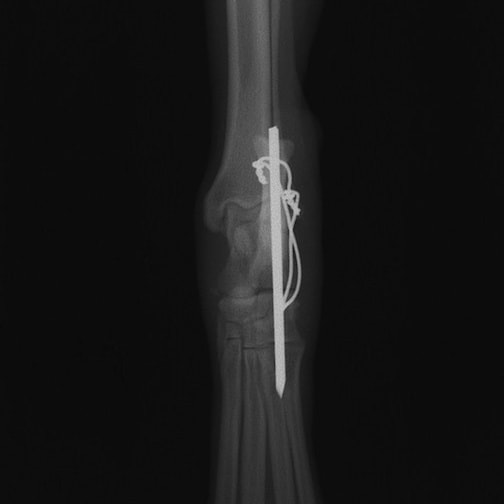

症例:柴犬 3歳

左後肢の完全挙上を主訴に来院されました。触診にて近位足根関節の過伸展を、レントゲン検査にて左足根関節周囲の軟部組織の腫脹、ストレス撮影によって距骨・踵骨と第4足根骨・中心足根骨間の脱臼および過伸展を認めました。

術中において、浅趾屈筋腱を剥離、内方へ牽引し、直接踵骨から第4足根骨までピンを挿入し(あらかじめ細いピンで下穴をあけておくとよい)、テンションバンドワイヤー法を併用し、関節軟骨の掻爬と海綿骨移植を実施しました。

術後レントゲン画像上に癒合が認められるまで約2ヵ月間は、運動を制限する必要があります。

術前正面像